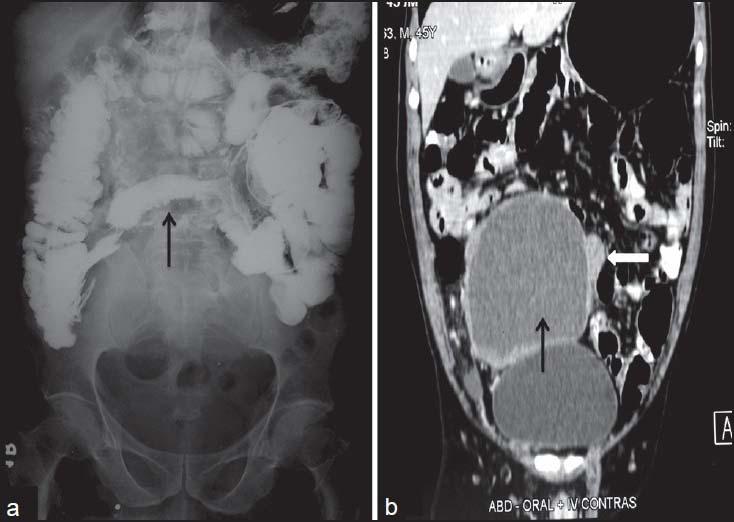

| Figure 11:Cystic gastrointestinal stromal tumors in a 51-yearold male — (a) barium meal follow through spot image showing displacement of terminal ileal loops (arrow) with extrinsic impression and obtuse angles (b) coronal contrast-enhanced computed tomography image showing cystic mass (arrow) arising from the ileal loop (arrowhead)

| Figure 11:Cystic gastrointestinal stromal tumors in a 51-yearold male — (a) barium meal follow through spot image showing displacement of terminal ileal loops (arrow) with extrinsic impression and obtuse angles (b) coronal contrast-enhanced computed tomography image showing cystic mass (arrow) arising from the ileal loop (arrowhead)